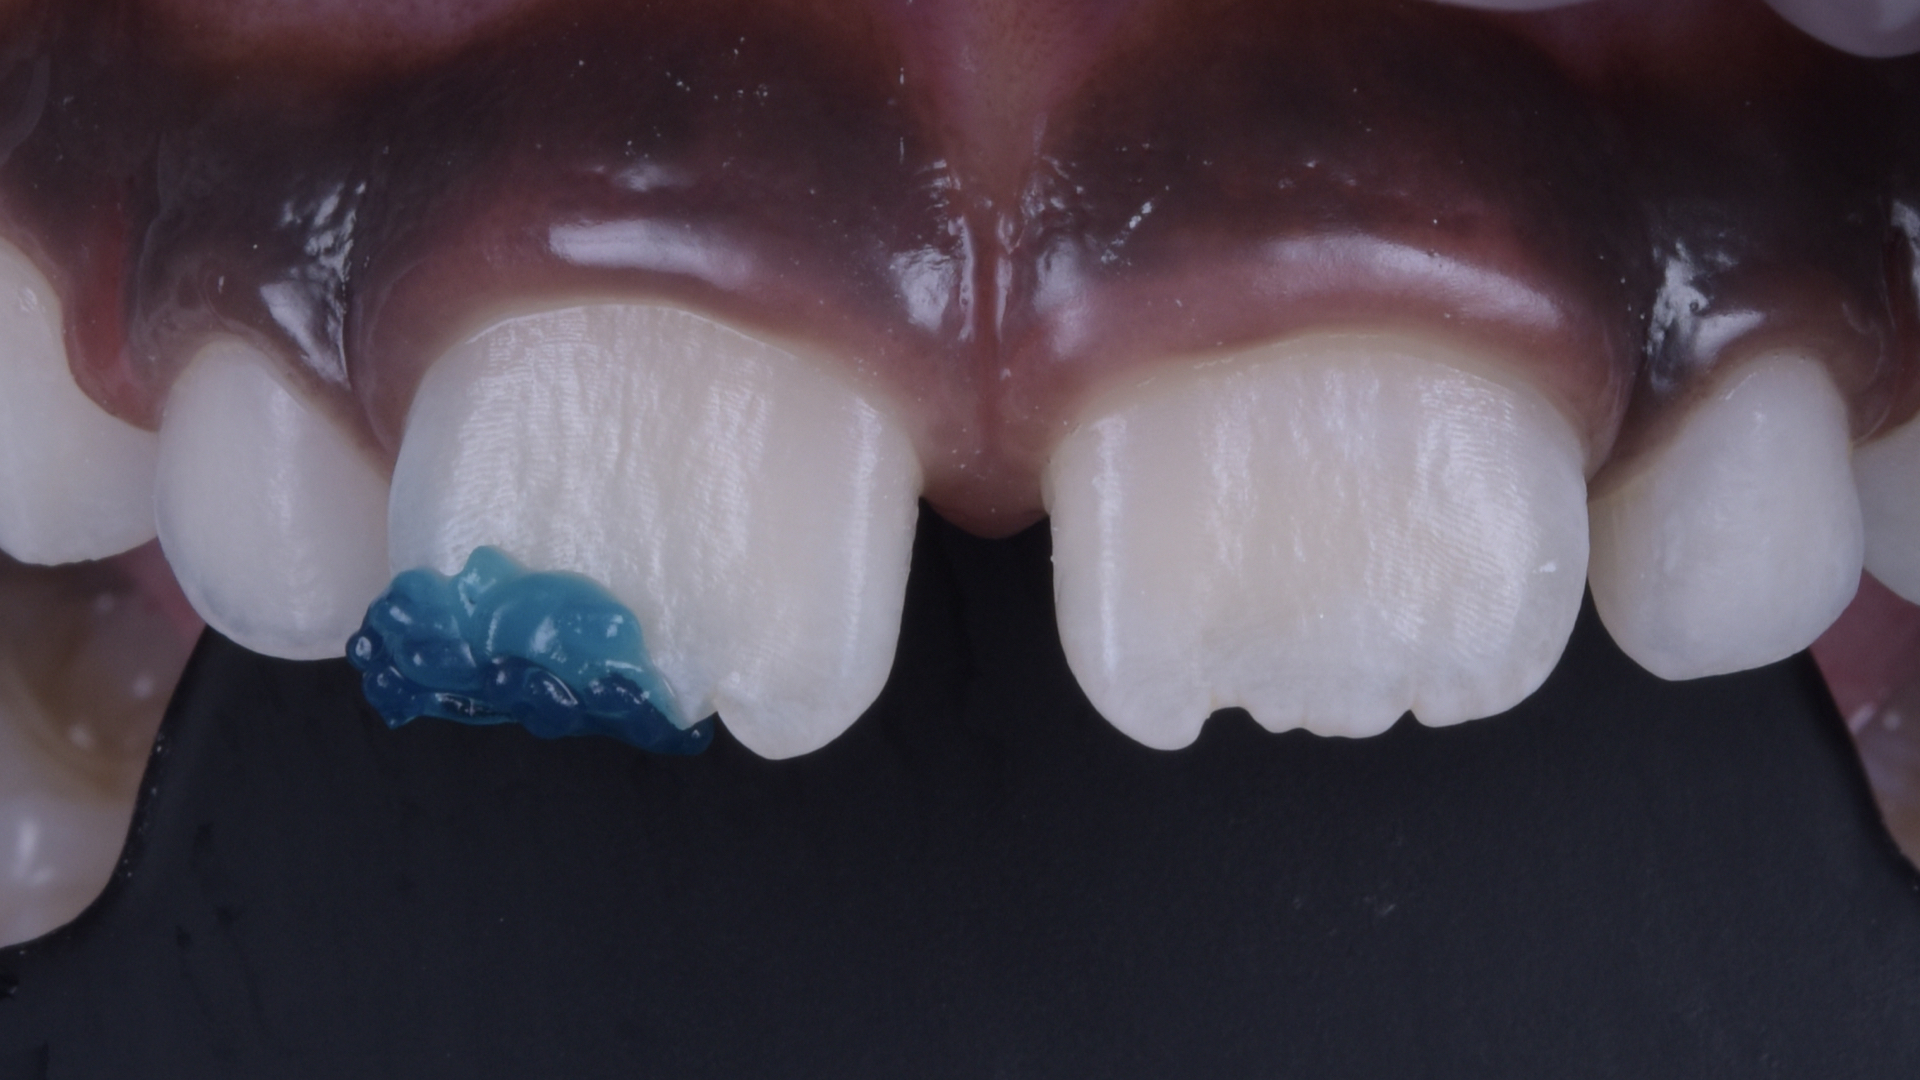

Behandlungsergebnis.

Ansicht des Zahnes 11 von lateral.

Restauration nach Fertigstellung.